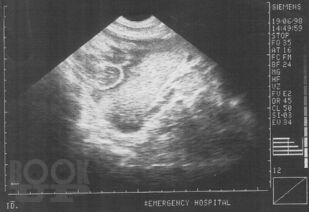

Ультразвуковая диагностика при закрытой травме органов брюшной полости и забрюшинного пространства

В монографии изложены основные достижения в диагностике закрытой травмы живота, приведены методики УЗИ с описанием эхосемиотики повреждений различных органов брюшной полости и забрюшинного пространства. Включены клинические примеры и большой иллюстративный материал, полученные в процессе собственных исследований. Приведен и аргументирован разработанный на кафедре госпитальной хирургии ВолгГМУ алгоритм диагностики и лечения сочетанной закрытой травмы живота, что определяет выраженную практическую направленность данной рукописи. Монография представляется весьма ценной для студентов старших курсов лечебных факультетов медицинских вузов, клинических ординаторов, практических врачей.